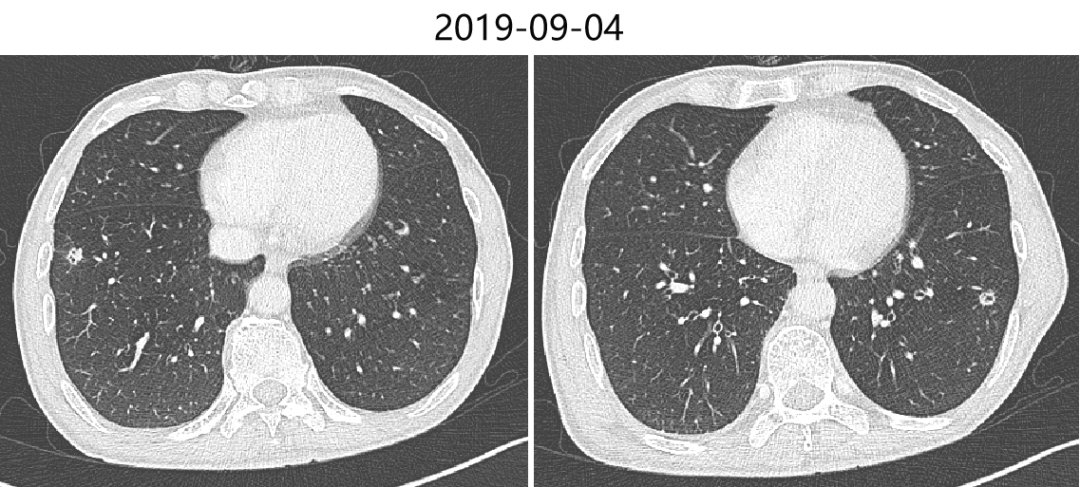

2019-09-04 [CT]示:双肺下叶结节,较前(2019-08-05)相仿,恶性可能大;双肺多发结节,较前相仿,转移可能;直肠K术后,胃术后,请结合临床;肝左叶占位,较前增大,考虑转移。

肺:双肺多发结节,较前相仿,转移可能。

肝:肝左叶占位,较前增大,考虑转移。